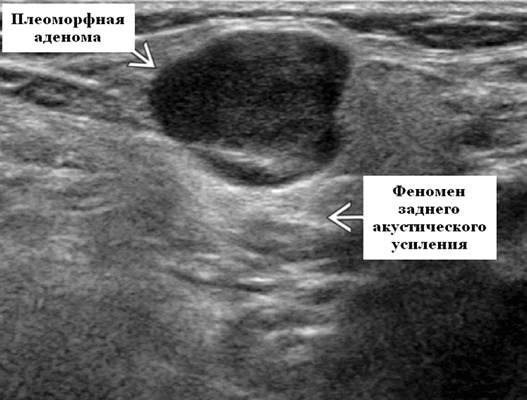

Доброкачественная смешанная опухоль подчелюстной железы при ультразвуковом исследовании

- Четко выраженная, плотная и гипоэхогенная опухоль на УЗИ по сравнению с прилегающей тканью слюнной железы.

- Однородная внутренняя эхо-структура с задним акустическим усилением

Общие особенности при ультразвуковом исследовании. Лучший диагностический признак: четко очерченная внутрижелезистая опухоль ПЧЖ, которая может выступать на ножке от края железы в поднижнечелюстное пространство (ПЧП), когда она становиться большой

Морфология. Малая плеоморфная аденома: одиночная, цельная, яйцевидная и хорошо разграниченная опухоль. Большая плеоморфная аденома на УЗИ: дольки ± кровоизлияние или некроз ± кальцификация

Серошкальное УЗИ. Хорошо выраженная, солидная и гипоэхогенная по сравнению с прилегающей тканью слюны. Однородная внутренняя эхо-структура с задним акустическим усилением. Опухоль имеет несколько тканевых границ и позволяет звуку легко проникать, вызывая улучшение заднего отдела. Большие опухоли могут иметь неоднородные внутренние эхосигналы из-за кровоизлияния и некроза. Гетерогенная плеоморфная аденома может иметь нечеткие границы, имитирующие злокачественную опухоль. Большие опухоли могут иметь дольки и появляться на ножке. Необычный кальциноз при ультразвуковом сканировании наблюдается при давней опухоли. Кожа и подкожные ткани в норме